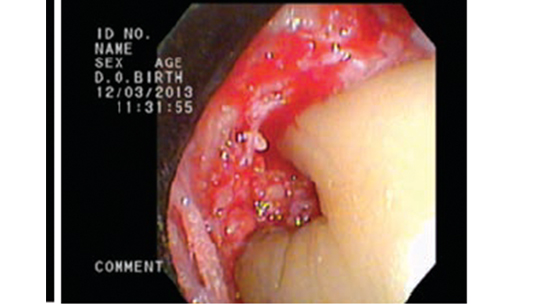

It's important to note that, while you can clean plaque off your teeth with brushing and flossing, hard tartar can only be removed by a professional cleaning, explains the American Academy of Periodontology (AAP). This type of calculus is usually dark brown to greenish black in color and can be detected with a dental instrument called an explorer. But the tartar that forms below the gumline - and is therefore not immediately visible - is known as subgingival calculus. Tartar that accumulates on your teeth above the gumline and is easily seen by your dentist or dental hygienist is called supragingival calculus, according to the IJDHS article. Once calculus forms, it then attracts more plaque, which in time can become another layer of calcified material. Calcification times can vary from person to person, depending on their salivary pH and the amount of calcium and other substances in their saliva. The average length of time for mineralization, however, is 10 to 12 days. Plaque can harden into calculus in as little as four to eight hours. This process is what creates calculus, a hard mass of bacteria stuck to your tooth surfaces. How Calculus DevelopsĪn article published in the International Journal of Dental and Health Sciences (IJDHS) explains that plaque, which is a sticky film of bacteria that constantly forms on your teeth, can mineralize due to the exchange of calcium and phosphate ions present in your saliva.

If left unremoved, subgingival calculus can lead to gum disease and tooth loss. Calculus is classified as either supragingival or subgingival, depending on its location on your teeth. This formation, also known as tartar, is a calcified mass that adheres to your teeth. When plaque builds up in your mouth, it can turn into an even greater dental health threat: calculus.